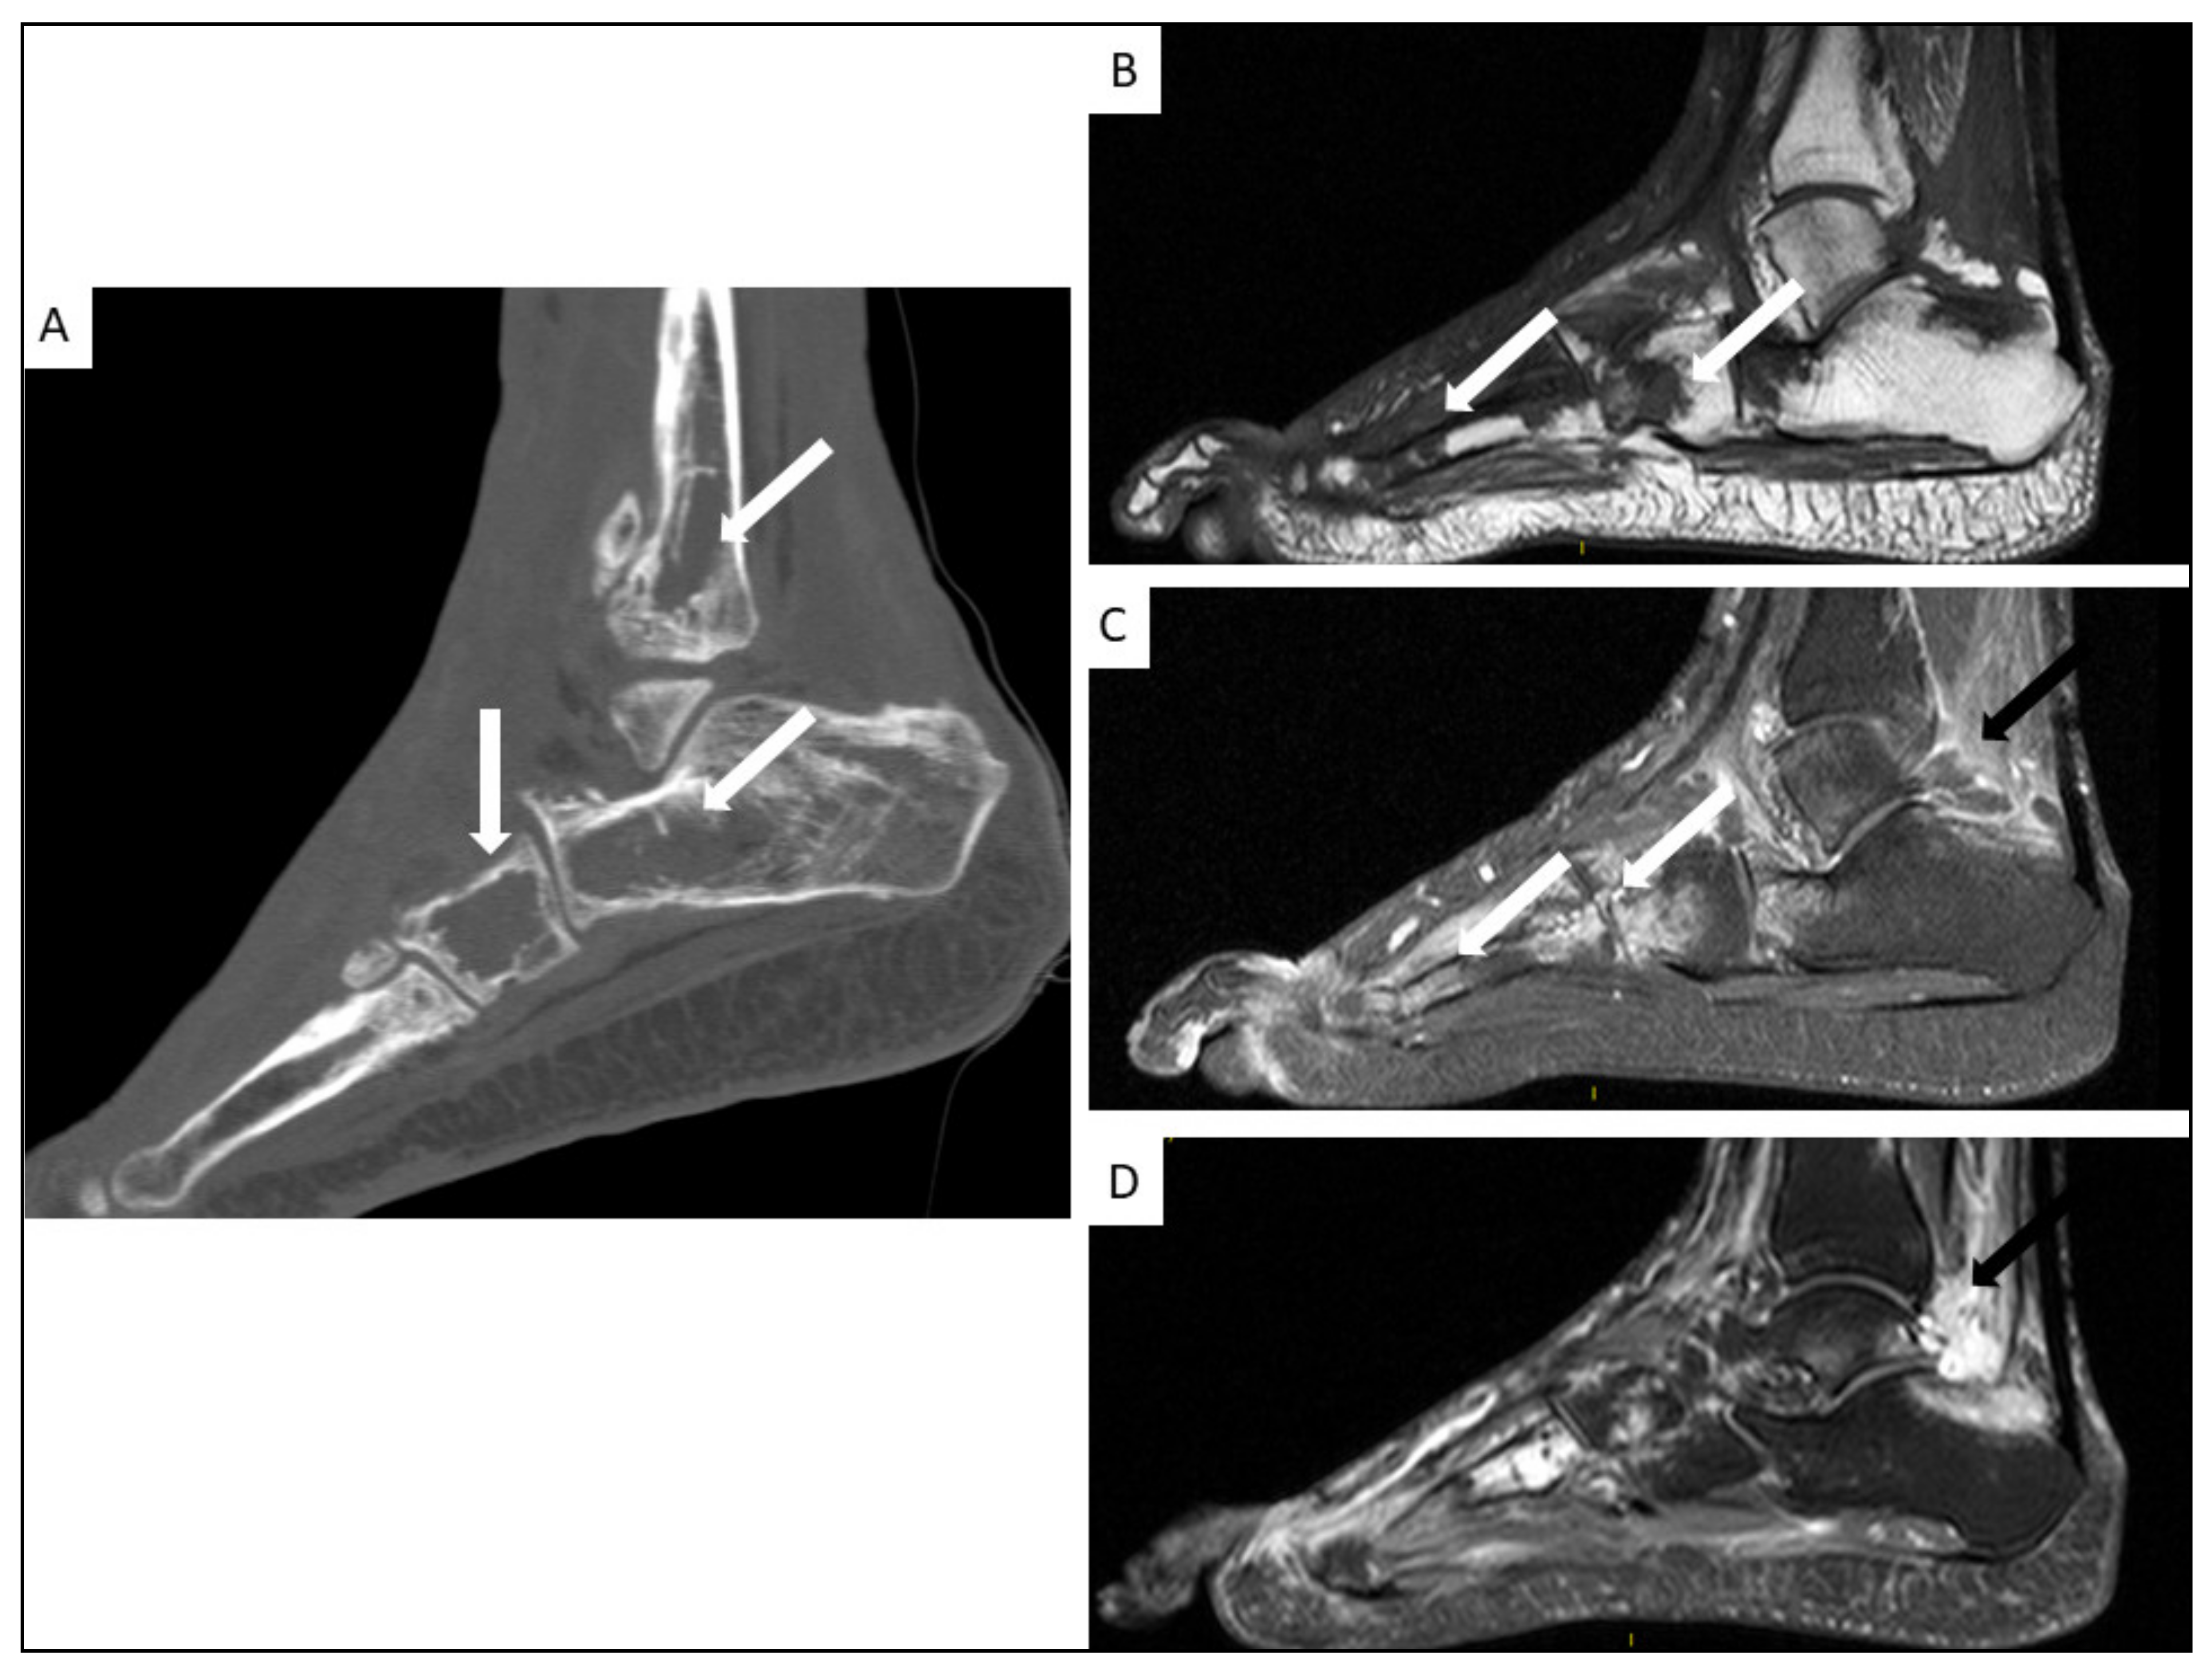

5.4. Musculo-Skeletal KS